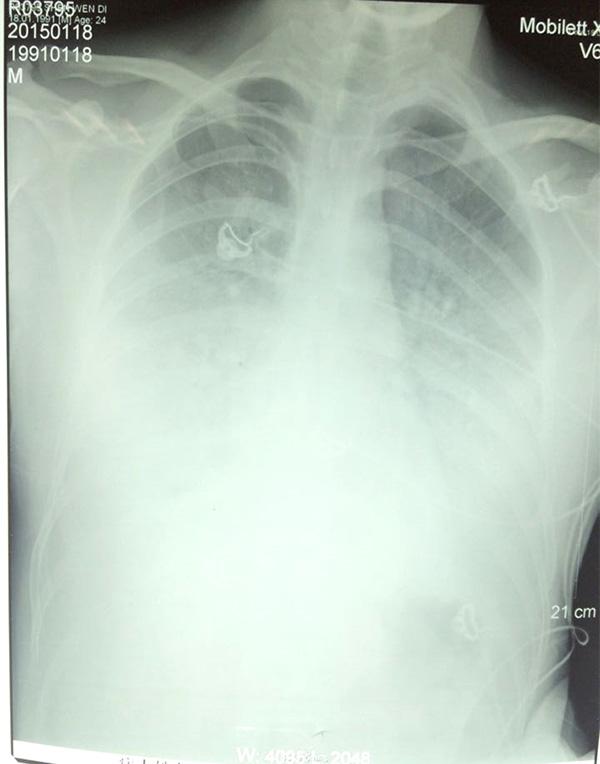

當(dāng)天下午,醫(yī)生通過(guò)會(huì)診,發(fā)現(xiàn)陶?qǐng)@的雙肺均有炎癥,出現(xiàn)“白肺”跡象,這說(shuō)明此時(shí)肺部已經(jīng)無(wú)法完成氧氣交換。而“白肺”最常見(jiàn)的病因是感染,其次是彌漫性肺泡出血綜合征、急性呼吸窘迫綜合征等。

陶?qǐng)@的肺部CT

1月18日,陶?qǐng)@使用氣管插管接呼吸機(jī)輔助呼吸;1月19日,病情持續(xù)惡化,白肺進(jìn)一步加重,CT上整個(gè)肺部幾乎都是白色;1月20日,三院專(zhuān)家和市第一人民醫(yī)院兩位專(zhuān)家以及來(lái)自上海第二軍醫(yī)大學(xué)附屬長(zhǎng)海醫(yī)院的專(zhuān)家經(jīng)過(guò)會(huì)診,決定最后使用CRRT(體外血液凈化以替代受損的腎功能)和ECOM(體外血液循環(huán)替代受損的心肺功能)試一下。